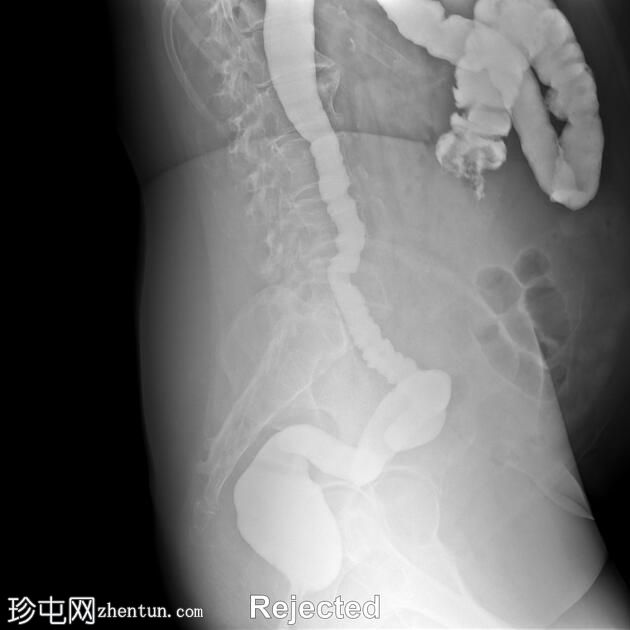

结肠异常表现包括结肠袋皱襞消失,使其外观模糊,呈铅管样改变。

其他异常表现包括降结肠和乙状结肠肠袢狭窄,以及横结肠和降结肠多处黏膜糜烂(双对比增强图像可见)。

未见肿块或瘘管形成。

升结肠外观正常,结肠袋皱襞完整。

结肠呈铅管状外观是慢性炎症性肠病(溃疡性结肠炎)的典型放射学表现。